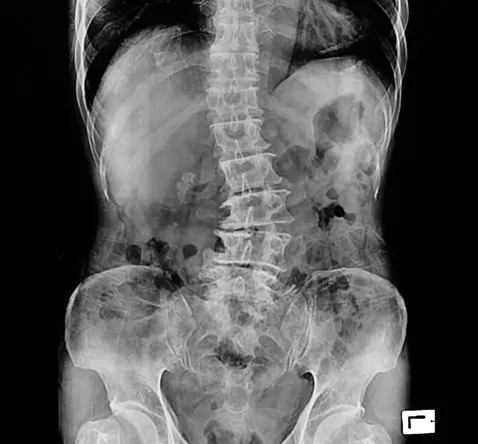

Our spines are meant to be our bodies’ central highways, straight, strong, and built for movement. But for some folks, the journey isn’t quite that direct. Scoliosis is a condition that causes the spine to curve sideways, sometimes twisting as it bends. It can develop in childhood, during a big growth spurt, or even appear later in life. At Marsch Chiropractic Center in Orangeburg, SC, we meet people every week who are surprised by a scoliosis diagnosis, but also relieved to learn it doesn’t have to define their future.

Not every case of scoliosis needs surgery or braces. For many people, especially those with mild to moderate curves, chiropractic care can make a meaningful difference in comfort and quality of life. At Marsch Chiropractic Center, we start with a thorough consultation and assessment, which may include posture checks or X-rays to get a clear map of your spine.